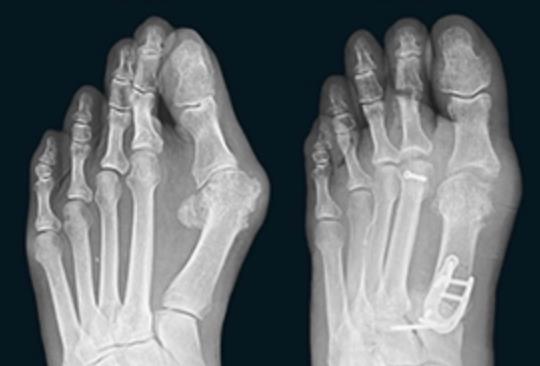

• LapiLock 4D Advanced Bunion Correction is described in manufacturer materials as a non-powered orthopedic manual bone positioner and jig system used for Lapidus bunion correction at the first tarsometatarsal joint, focusing on realigning and fusing the first metatarsal–medial cuneiform articulation rather than simply shaving the medial eminence.

• By shifting the correction proximally and addressing rotation, intermetatarsal divergence, and sagittal plane malalignment at the first tarsometatarsal joint, the system is intended to achieve a more anatomic and stable first-ray alignment than procedures that focus only on distal metatarsal osteotomy.

• LapiLock serves as a triplanar bone positioner and joint preparation system; definitive fusion of the first metatarsometatarsocuneiform joint is achieved with plate, screw, and staple constructs from the Fusion Orthopedics portfolio, selected at the surgeon’s discretion once correction is obtained.

• Manufacturer materials list 13 or more fixation options compatible with the system, including a U-Plate, a Neutral Lapidus Plate, Dual Slim constructs, T-Plate configurations, dual Lapidus plates, and two-plate constructs for more robust medial column constructs.